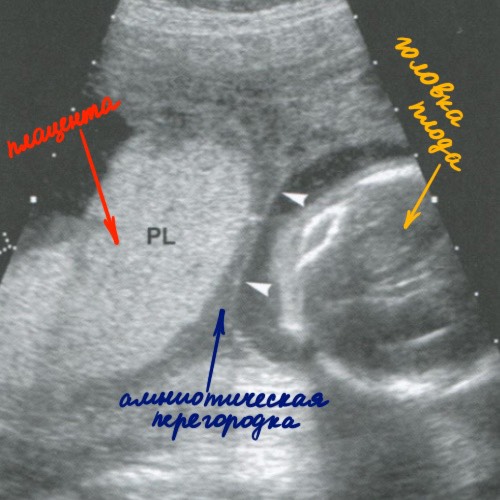

Амниотическая перегородка никогда не разделяет плодный пузырь на две части, хоть на УЗИ в определенных срезах может так показаться. И самое главное, амниотическая перегородка в отличие от амниотических тяжей никогда не прикрепляется к плоду, а значит не приносит ему никакого вреда. Иногда даже плацента может лежать на этой перегородке.

А когда плод вырастает, он чаще всего эту перегородку «придавливает» к стенке плодного пузыря, именно поэтому на 3 скрининге у меня ее уже не увидели) Но, так же пишут, что в некоторых случаях перегородка может мешать плоду принять правильное положение головой вниз.